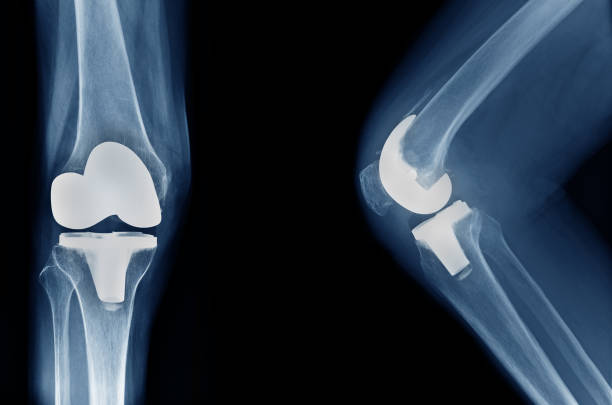

During knee replacement surgery, deteriorated knee joint components are removed and replaced with ceramic, metal, or plastic artificial parts. There are two categories for the procedure:

4. The implant's placement : The artificial parts are installed and secured. The replacement joint usually consists of a plastic spacer that facilitates smooth mobility and metal components for the tibia and femur. In certain instances, a plastic component may also be used to resurface the kneecap.